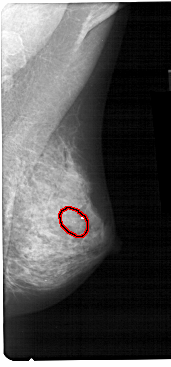

A_1472_1.LEFT_CC

LEFT_CC LINES 4891 PIXELS_PER_LINE 2236 BITS_PER_PIXEL 12 RESOLUTION 43.5 NON_OVERLAY

FILE: A_1472_1.RIGHT_CC.OVERLAY

TOTAL_ABNORMALITIES 1

ABNORMALITY 1

LESION_TYPE CALCIFICATION TYPE PLEOMORPHIC DISTRIBUTION CLUSTERED

ASSESSMENT 4

SUBTLETY 4

PATHOLOGY BENIGN

TOTAL_OUTLINES 1

BOUNDARY